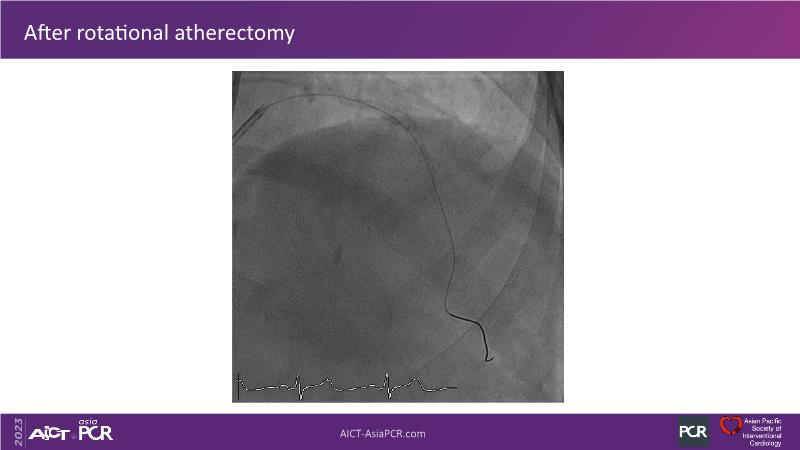

• To see advantages of RotaCUT as part of lesion preparation in left main bifurcation